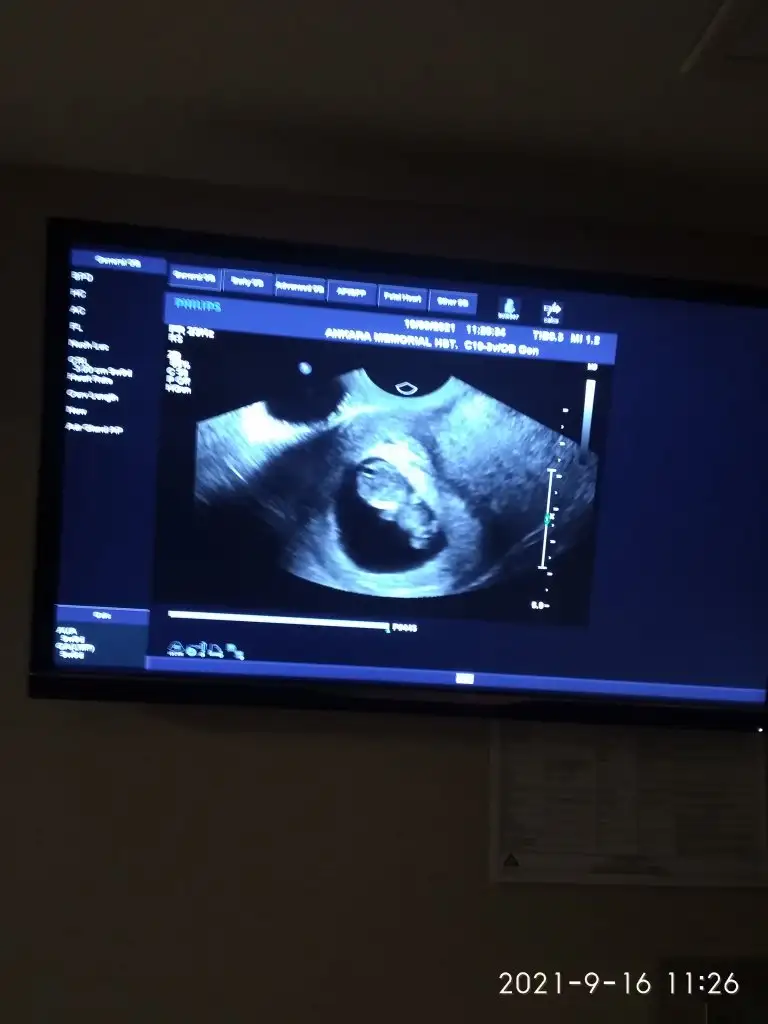

Canlanmaya başlamış çocuğum hareket ediyodu kolları çok güzel bı duyguymua bu rabbim herkesin kucağını doldursun kucağı boş kalmasın herkes yaşasın inşallah

Canlanmaya başlamış çocuğum hareket ediyodu kolları çok güzel bı duyguymua bu rabbim herkesin kucağını doldursun kucağı boş kalmasın herkes yaşasın inşallah![]()